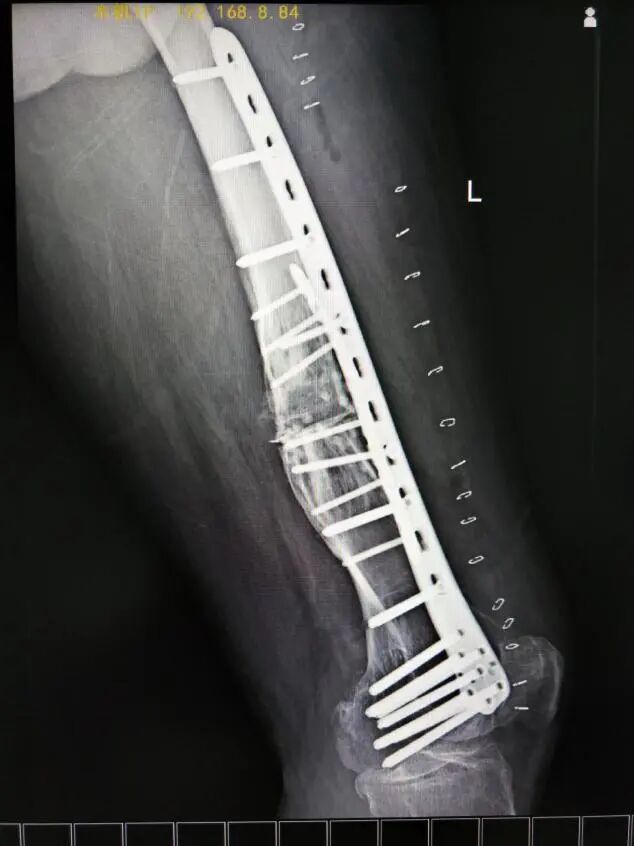

術(shù)中,醫(yī)療團(tuán)隊按照預(yù)定手術(shù)思路,首先沿左大腿中下段外側(cè)縱形作皮膚切口,安裝股骨前方截骨導(dǎo)板,用擺鋸沿截骨導(dǎo)板截斷股骨畸形最大處,預(yù)留股骨干外側(cè)部分皮質(zhì)。然后用撐開器沿截骨端將其撐開并放置內(nèi)側(cè)楔形導(dǎo)板,在C臂機(jī)透視下見經(jīng)截骨矯形后現(xiàn)股骨干向內(nèi)、向后成角畸形基本恢復(fù),力線基本糾正。最后進(jìn)行左側(cè)股骨鋼板內(nèi)固定術(shù)+左側(cè)髂骨切除術(shù)用作移植物+左側(cè)股骨植骨術(shù)+左側(cè)股骨人工骨植骨術(shù)。整個手術(shù)過程非常順利。

術(shù)中鋼板螺釘固定后影像

術(shù)后復(fù)查X線片影像(正位)